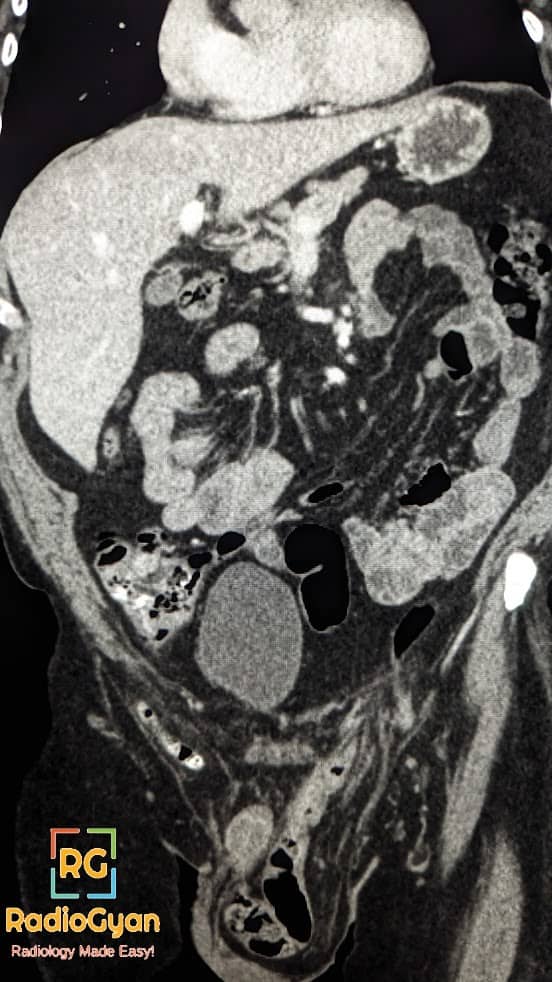

Amyand hernia is a rare type of inguinal hernia where the appendix is found within the hernia sac.

Imaging features of an Amyand hernia include a blind-ending tubular structure arising from the cecum and extending into the inguinal sac, with or without inflammatory changes.